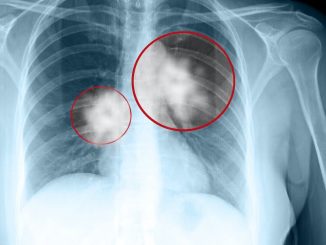

Gene and cell therapies to combat pancreatic cancer

03.06.2023

Pancreatic cancer is an incurable form of cancer, and gene therapies are currently in clinical testing to treat this deadly […]